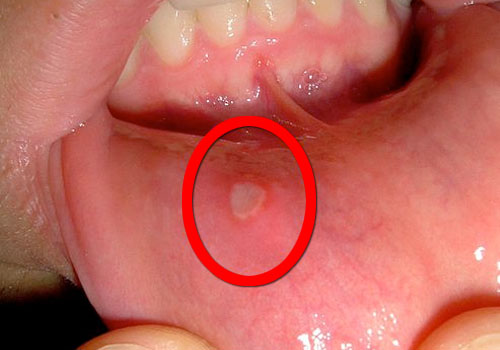

Blancs, ou jaunes, les aphtes sont de petits ulcères douloureux pouvant apparaître dans la bouche, ils sont généralement entourés par un cercle rouge et brillant. Mais savez-vous comment prévenir les aphtes ?

- Des taches rouges et douloureuses qui se transforment ensuite en ulcère ;

- Un ulcère de couleur jaune ;